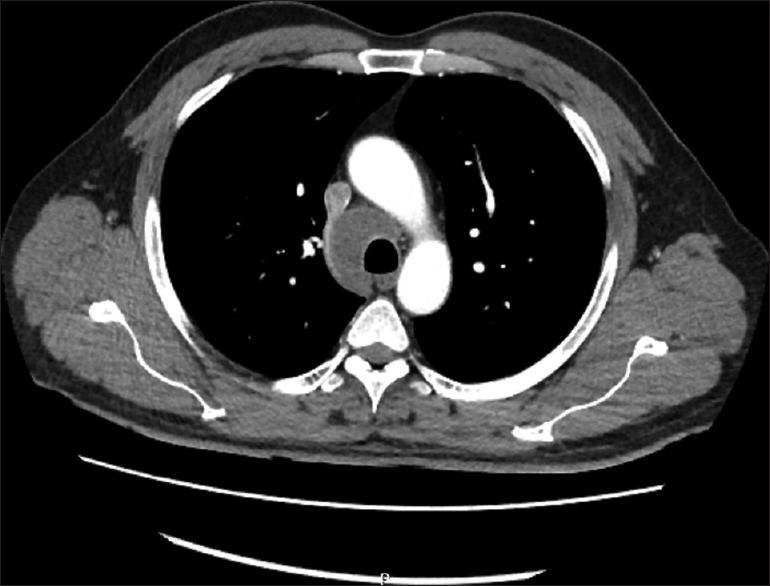

A rare complication of endobronchial ultrasound-guided transbronchial needle aspiration: Pericardial empyema.

Endobronchial ultrasound (EBUS)-guided transbronchial biopsy procedure is widely used for the diagnosis of mediastinal lymphadenopathy. İt is a safe method and the complication rate of procedure is <1%. Rarely, the fatal complications may develop after the intervention. Here, we present a case of pericardial empyema occurred as a complication of EBUS-guided transbronchial biopsy procedure.